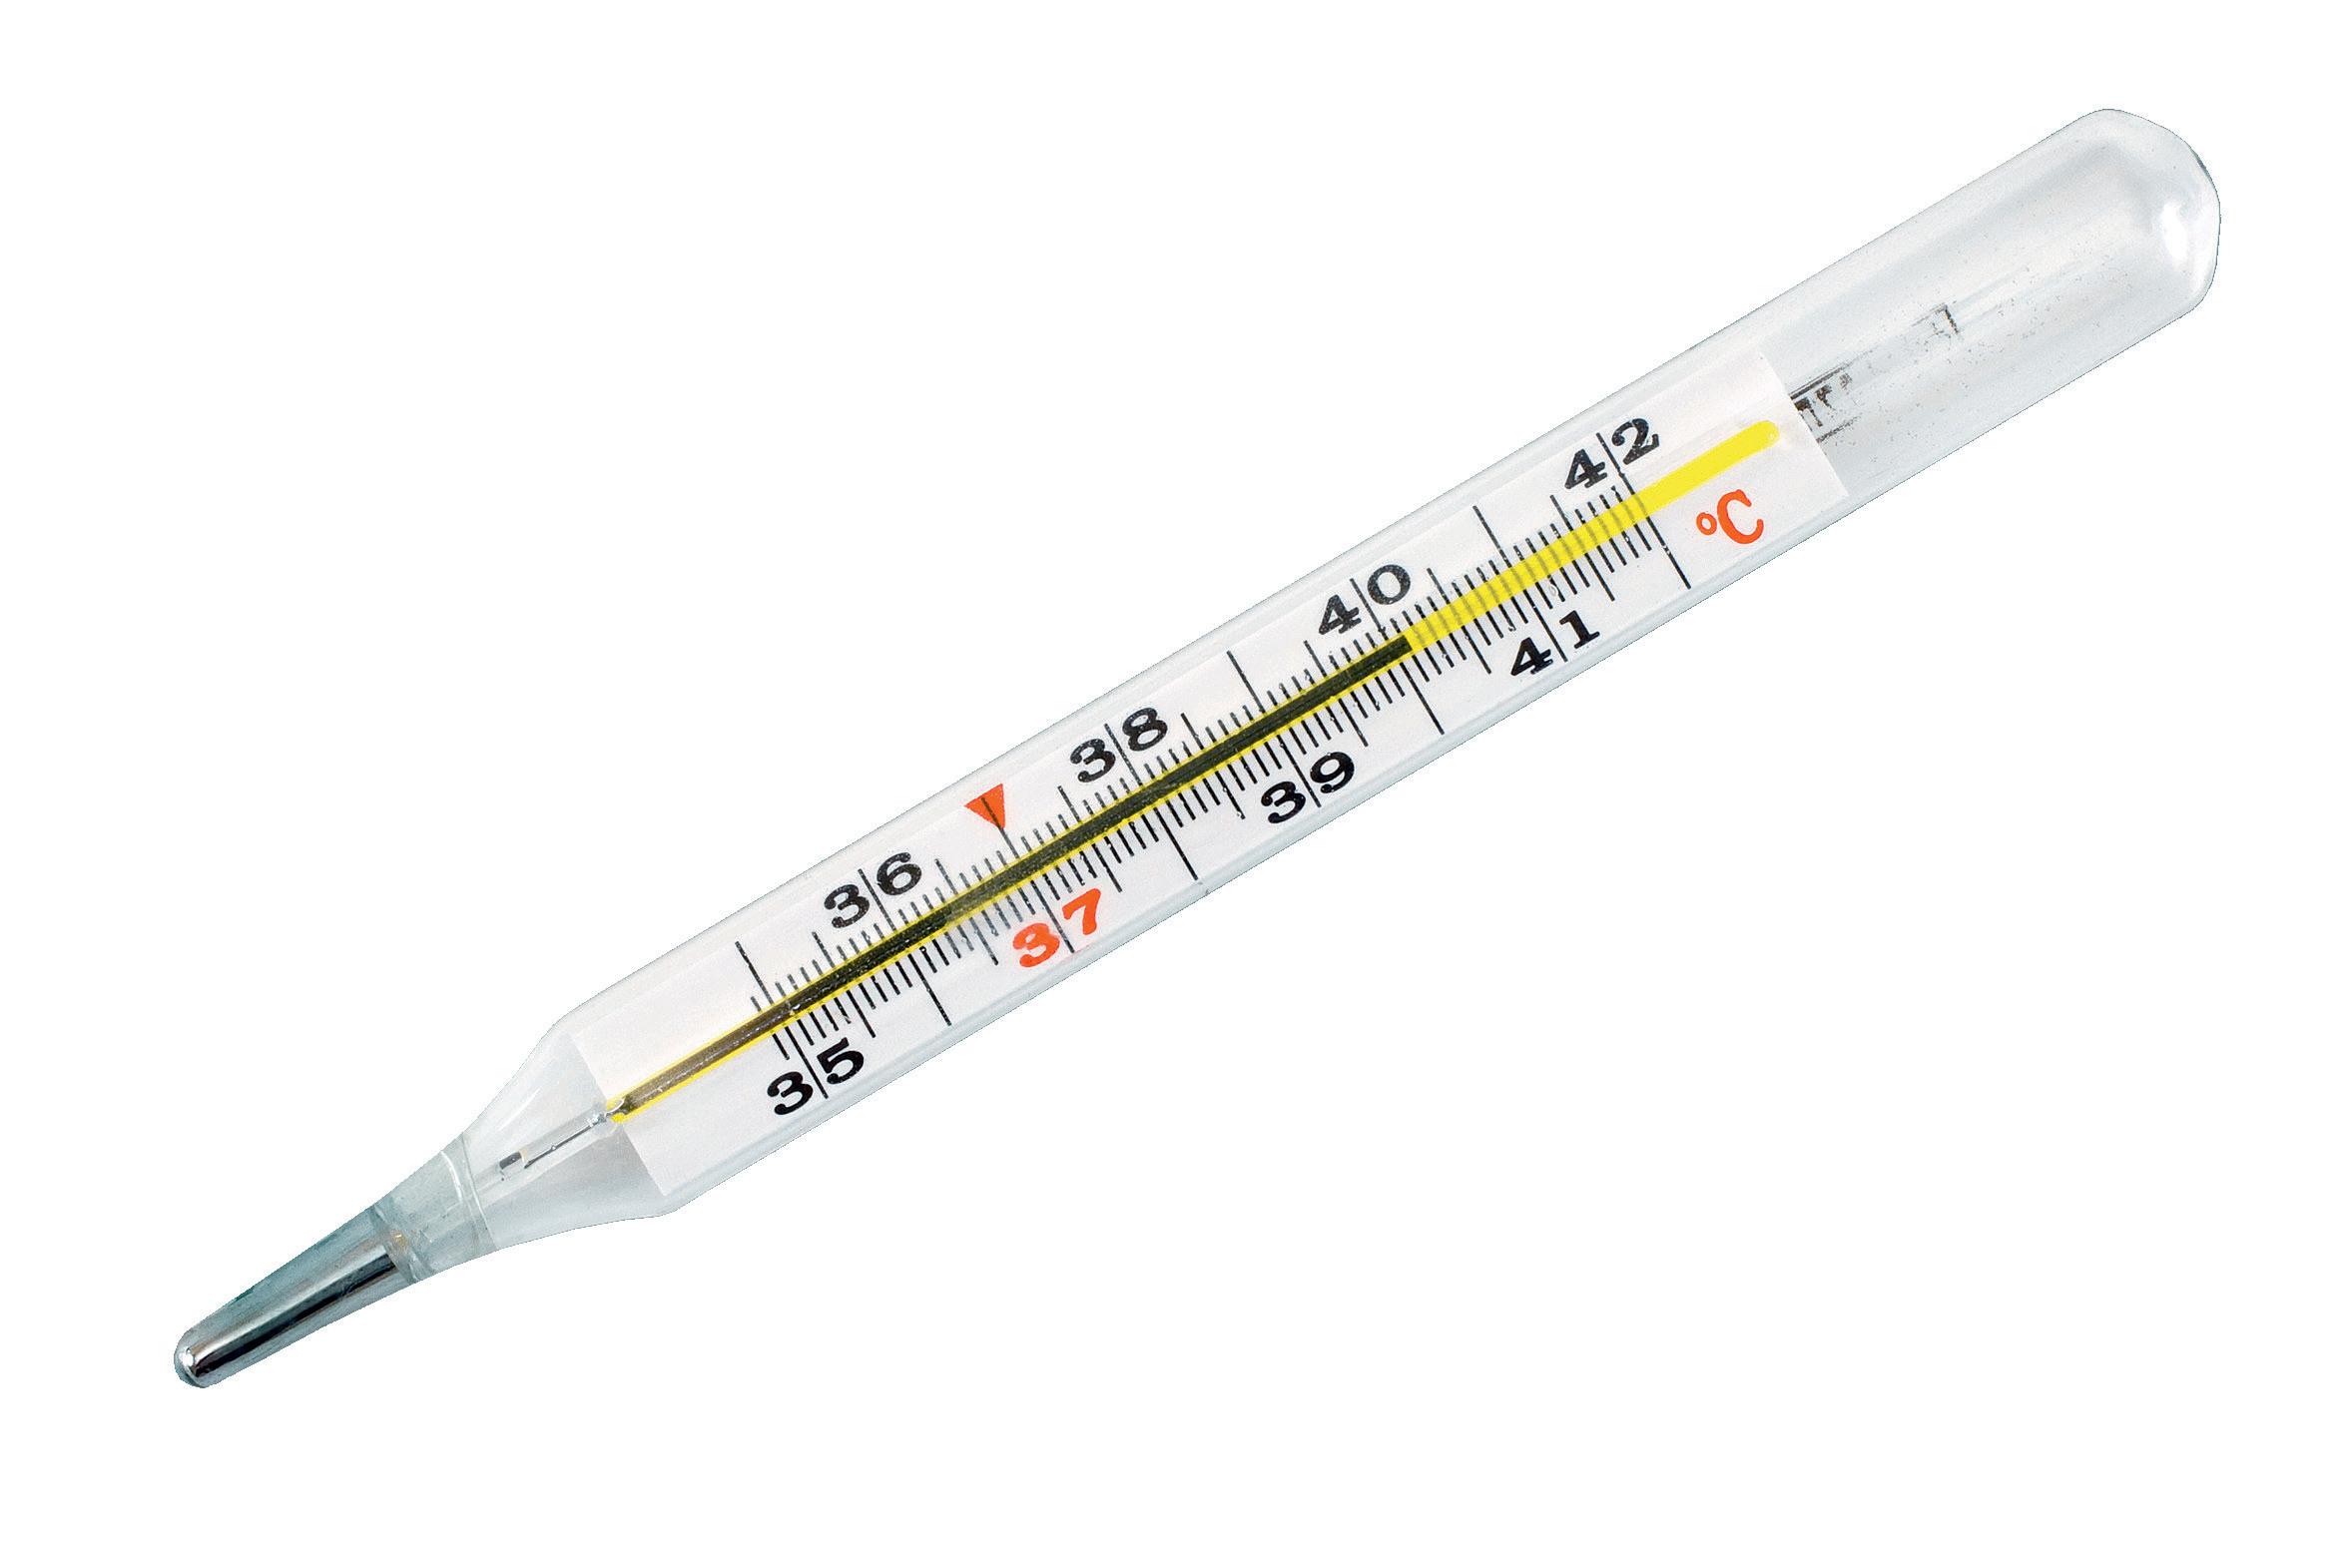

Fieber lenken statt senken

Fieber ist das wichtigste Abwehrmittel gegen Viren. Grippeviren sind temperaturabhängig, wenn man das Fieber künstlich senkt, begünstigt man die Vermehrung der Erreger. Das Fieber klingt in der Regel nach zwei bis drei Tagen ab. Ab wann ist zusätzlich Fiebersenkung angesagt? Ab 39 Grad Fieber empfehlen sich Zitronenwadenwickel oder Essigsocken.

Wenig Nebenwirkungen

Wichtig dabei ist, dass die mittels Hyperthermie erzeugte Erwärmung selektiv, das heisst nur im Tumorgewebe erfolgt. Das angrenzende gesunde Gewebe kann die Wärme durch eine stärkere Durchblutung leicht ableiten und hält seine Temperatur bei rund 37 bis 38 Grad Celsius. Diese Fähigkeit hat das Tumorgewebe aufgrund seiner primitiveren Blutversorgung verloren. Die gestörte Blutzirkulation im Tumorgewebe führt zu einer unzureichenden Wärmeregulierung und damit zu einem Hitzestau, sodass die Wärme ihre